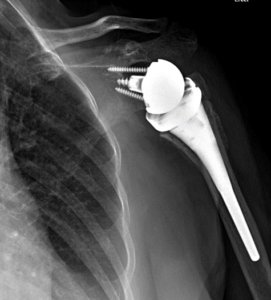

Dr. Riehl treats orthopaedic conditions both operatively and nonoperatively and performs a wide array of orthopaedic procedures including, but not limited to, the following:

Hip, knee, and shoulder replacement including direct anterior total hip arthroplasty